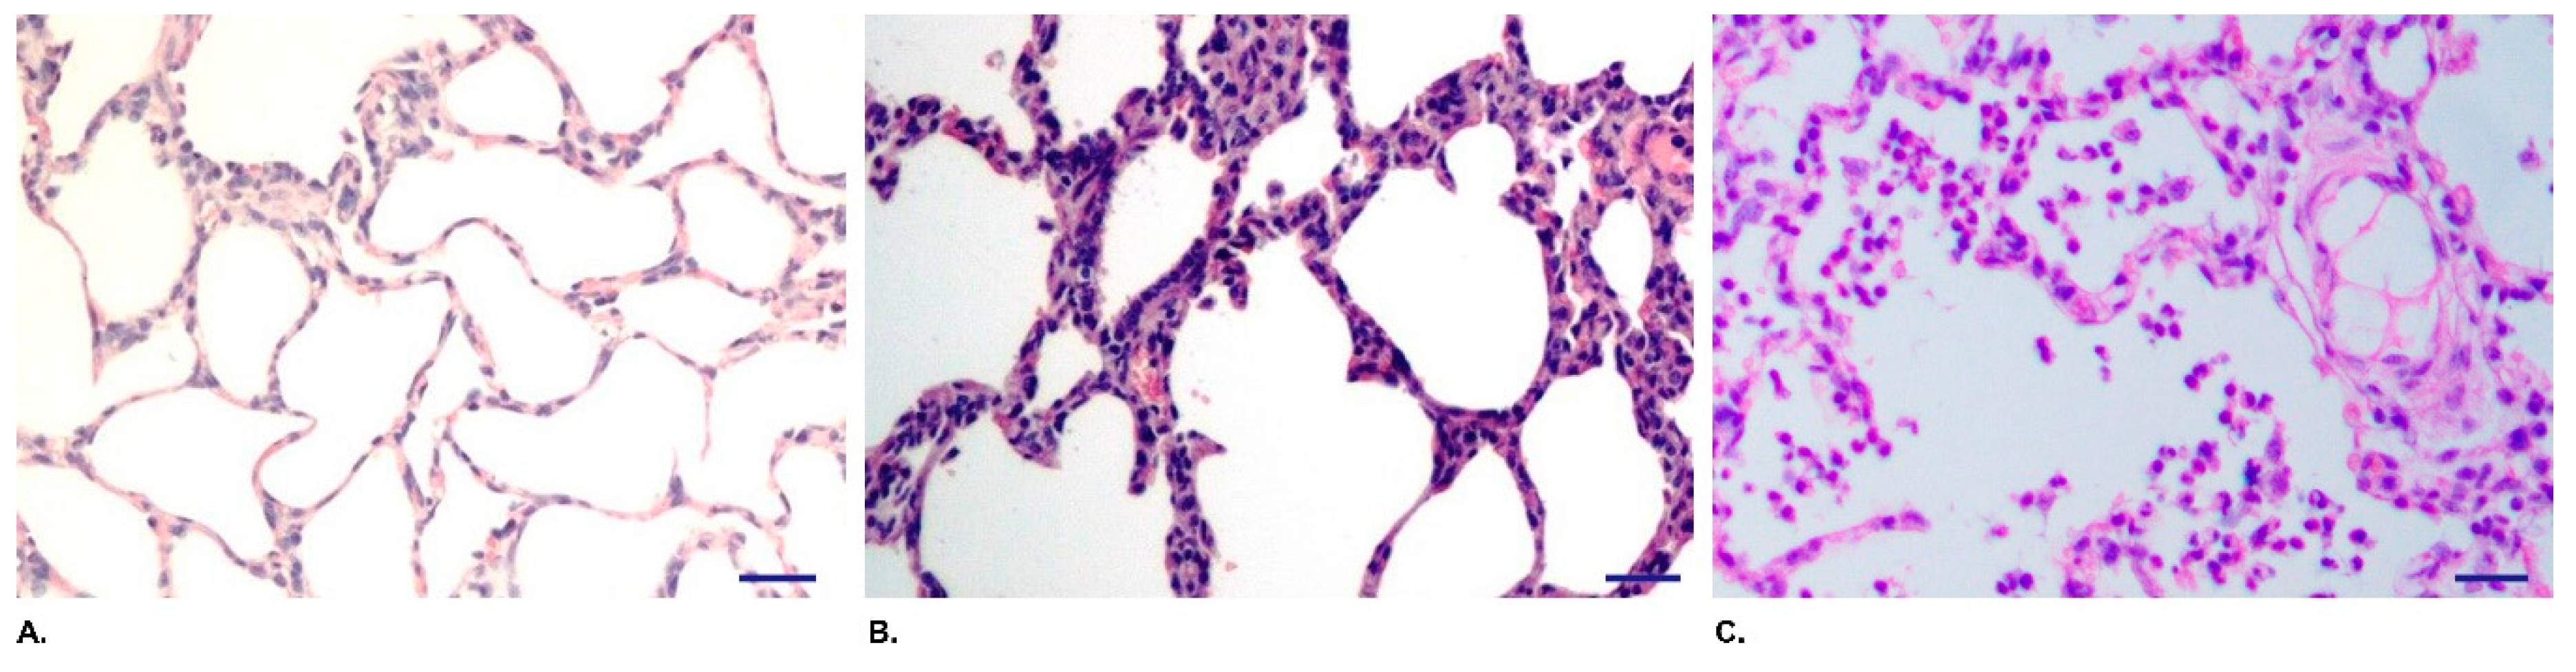

3.2. QH09 Showed Attenuated Virulence and Capacity of Colonization in Mice

3.3. QH09 Was Safe to Piglets